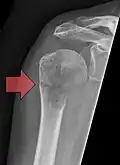

- Vues de fractures pathologiques

Fracture pathologique de l'humérus sur une métastase de carcinome du rein

Fracture pathologique du bras gauche sur une métastase osseuse de cancer du sein

Scintigraphie corps entier avec 99mTc-HDP de la patiente avec une fracture du bras due à une métastase du cancer du sein